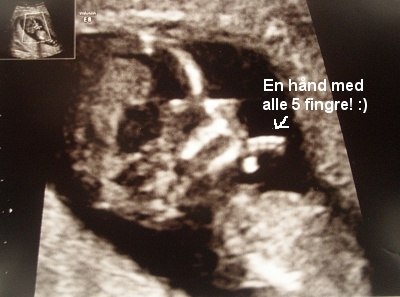

Vi så både arme, ben, og en hånd med alle 5 fingre. Alt er normalt! Navlestrengen så normal ud, kraniet så normalt ud, alt var perfekt.

Her er lige et par fotos af lille blypper!